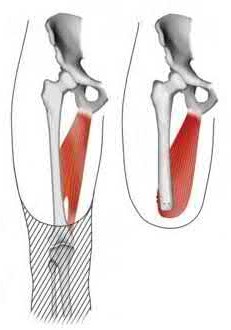

Figure A demonstrates a displaced subtrochanteric femur fracture with an intact lesser trochanter. The pull of iliopsoas on the lesser trochanter as well as the intact external rotators and gluteal musculature results in the the proximal fragment being in a flexed and externally rotated or abducted position (the most common post operative deformity). Reduction manuevers must be biologically friendly but also counteract the flexion/abduction moment. Lundy's review article discusses evaluation and treatment of subtrochanteric fractures. The review article details the various implants often used which include 95 degrees plates, femoral reconstruction nails, or trochanteric femoral nails with interlocking options. Lundy's article discourages the use of the 135 degree screw and side plate combo due to high failure rates in these fracture patterns. Bedi et al also review treatment of these fractures and discuss common

problems of malunion, nonunion, and implant failure. The article reviews reduction techniques that are soft tissue friendly, as well as the use of appropriate implants in these fracture types.

A 35-year-old-male sustains the fracture seen in Figure A. Which of the following reduction forces must be applied to the proximal fragment to correct the deformity commonly seen in these fractures?